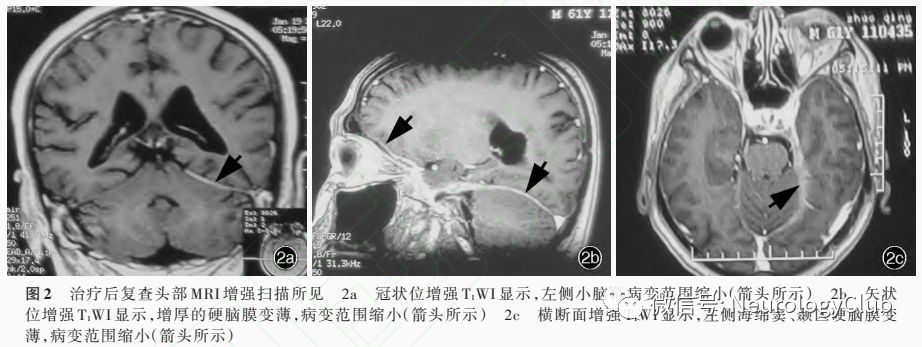

诊断与治疗经过  临床诊断为抗中性粒细胞胞质抗体相关血管炎,继发性肥厚性硬脑膜炎(HP)。为排除感染,明确病理性质后指导治疗,建议行硬脑膜组织活检术,患者及其家属顾虑相关风险拒绝。予泼尼松50mg/次、1次/d口服,每2周减量5mg,莫昔沙星0.40g/次、1次/d口服抗感染,曲马朵50mg/次、1次/晚口服镇痛,治疗10d后肝功能试验明显升高,考虑药物相关肝损伤可能,停用莫昔沙星和曲马朵,改为必需磷脂(易善复)456mg/次、3次/d和甘草酸二铵(甘利欣)150mg/次、3次/d口服改善肝功能,体温恢复正常,症状明显好转。患者共住院28d,出院后1个月门诊随访,症状无反复,复查增强MRI显示,增厚的硬脑膜变薄,强化征象减轻,病变范围缩小(图2)。